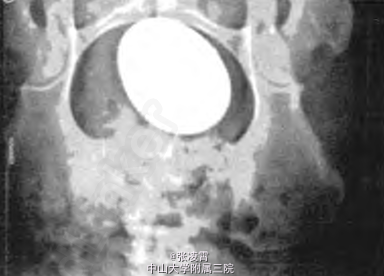

查体:生命体征无异常,心肺未见异常,下腹部压痛,下腹部正中可触及1个包块,质硬,约13 cm×12 cm。 实验室检查:血钙2.46 mmol/L,血磷1.67 mmol/L;白细胞11.5×109/L;肾功能未见异常;尿常规:白细胞满视野/HP; B超示:膀胱区域呈现强回声后伴有声影,12.8 cm×11.0 cm×10.9cm。 腹部平片示:盆腔膀胱区域呈现有一椭圆形分层致密高密度影,12 cm×11 cm×10 cm。

诊断:膀胱结石。 予完善相关术前准备,查无明显手术禁忌。对该例患者进行耻骨上膀胱切开取石,取出膀胱结石的实测尺寸为:10.6 cm×9.00cmX 7.9 cm,重量446 g。